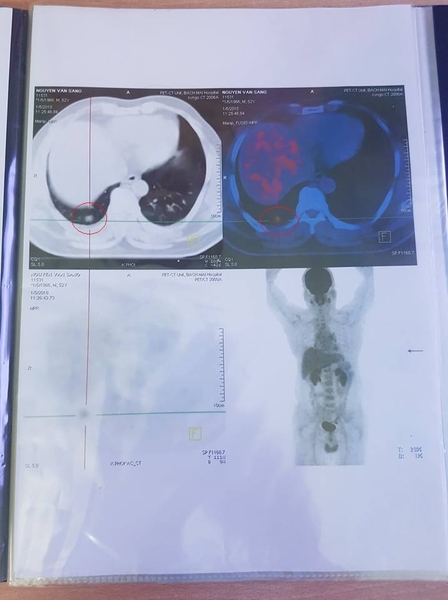

1. NGUYỄN VĂN SANG - Nam: 52 Tuổi

Địa chỉ: Văn Giang – Hưng Yên

Phát hiện ung thư phổi phải tháng 12/2016, đã mổ tại BV Phổi Trung Ương, sau mổ BN điều trị hóa chất tại trung tâm ung bướu BV Bạch Mai, kết thúc điều trị vào tháng 7/2017, khám định kỳ tháng 10/2017 hoàn toàn ổn định.

Tháng 1/2018 BN ho nhiều, mệt. Đến BV Bạch Mai khám kiểm tra và được chụp PET/CT phát hiện tổn thương di căn thùy dưới phổi phải KT 1,3 x 1,3 x 2,1cm, di căn hạch phế quản gốc phải KT 0,8 x 1,4cm.

Kết quả chụp PET/CT trước khi uống Kilcel 500mg